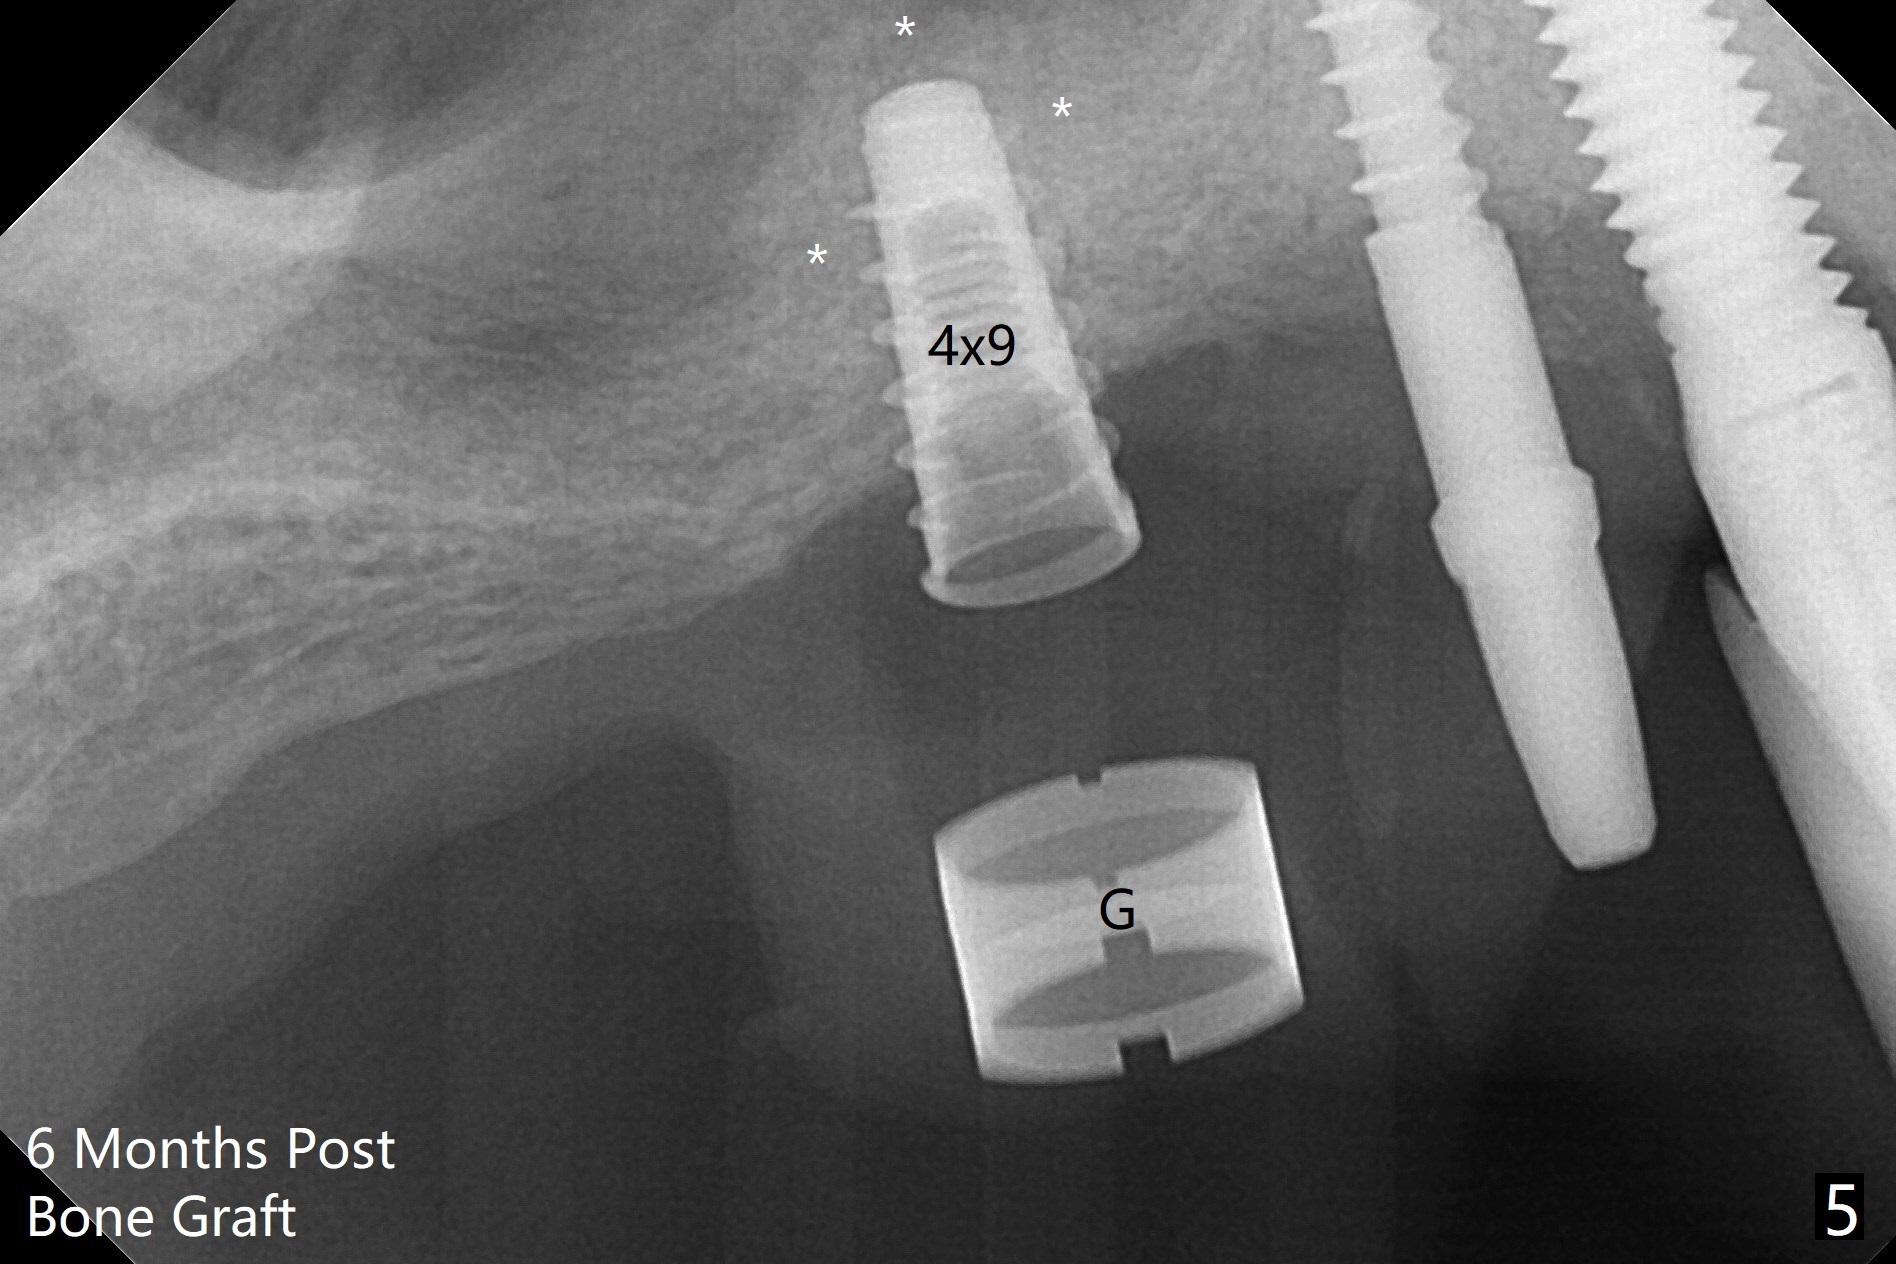

术前清晨复习3号牙窦底,中央是植骨(图一,二:*(皮质骨:密度高,质地可能软)),由于窦底斜坡,术前估计穿孔可能最先发生在远中,术中的确如此(图三:<(使用4毫米钻头后)),放置粘性骨粉(图四),利用导板(图五:G)和4x9毫米报废植体提升(*)。使用4.5毫米钻头,放置半张PRF膜,骨粉,5x7毫米植体以及修复基台,最后在后两者周围放置骨粉(图六,七:*(腭侧一个螺纹暴露)),覆盖1/2PRF膜,缝合,树脂敷料。